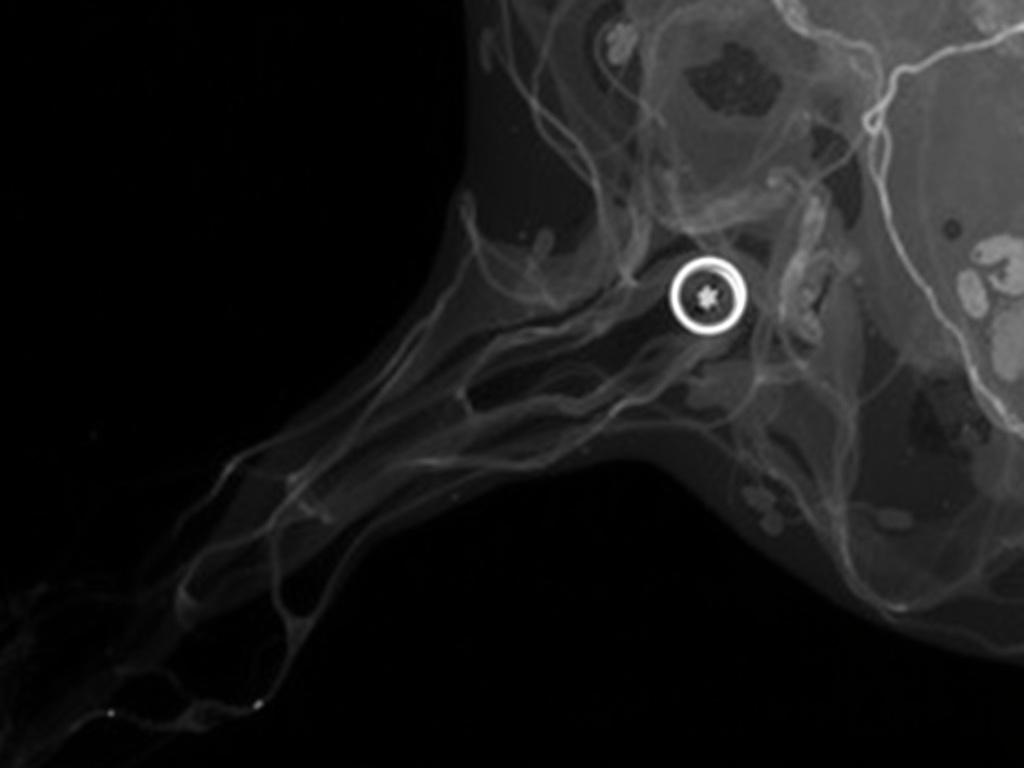

Если основной симптом — выделения из соска, целесообразно сделать дуктографию (рентген с контрастом протоков) или вспомогательные методы вроде молочной скопии. Современная магнитно-резонансная томография (МРТ) показывает лучшее расположение и сосудистую структуру опухоли, но применяется не всегда.